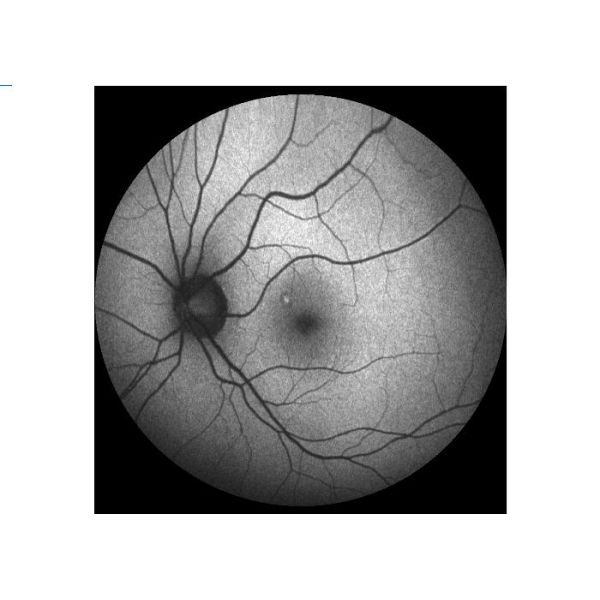

Fluorescencia auto (AF) | Para registrar la distribución material fluorescente del fondo en la condición normal o de la patología |